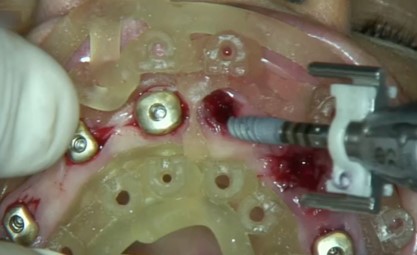

Durante l'intervento chirurgico si posizionava la guida (Fig. 3a) e i siti implantari venivano fresati secondo le sequenze previste. Posizionavamo gli impianti (LYRA ETK, Sallanches, Francia) e gli abutment iPhysio® Profile Designer (Fig. 3 b) che erano selezionati in base al profilo di emergenza desiderato del futuro restauro.

Questi healing abutments vengono avvitati sugli impianti durante la prima o la seconda fase chirurgica. Essi poi restano in posizione durante tutta la guarigione ossea e gengivale e durante la presa dell'impronta, indipendentemente dall'area di impianto. Il Profile Designer iPhysio® viene essere rimosso solo una volta, per posizionare il restauro finale. Gli abutment provvisori in polieter-eter-chetone (PEEK) venivano agganciati agli iPhysio® Profile Designers, sui quali venivano adattati i restauri provvisori (Fig. 3c). Il carico immediato degli impianti è stato eseguito utilizzando una protesi provvisoria in PMMA (Fig. 3d). Al rientro per un controllo, si osservava una corretta guarigione dei tessuti attorno agli impianti e attorno agli abutment iPhysio®.

Posizionamento degli impianti attraverso la dima chirurgica

Fig. 3(a)  Posizionamento degli impianti attraverso la dima chirurgica.